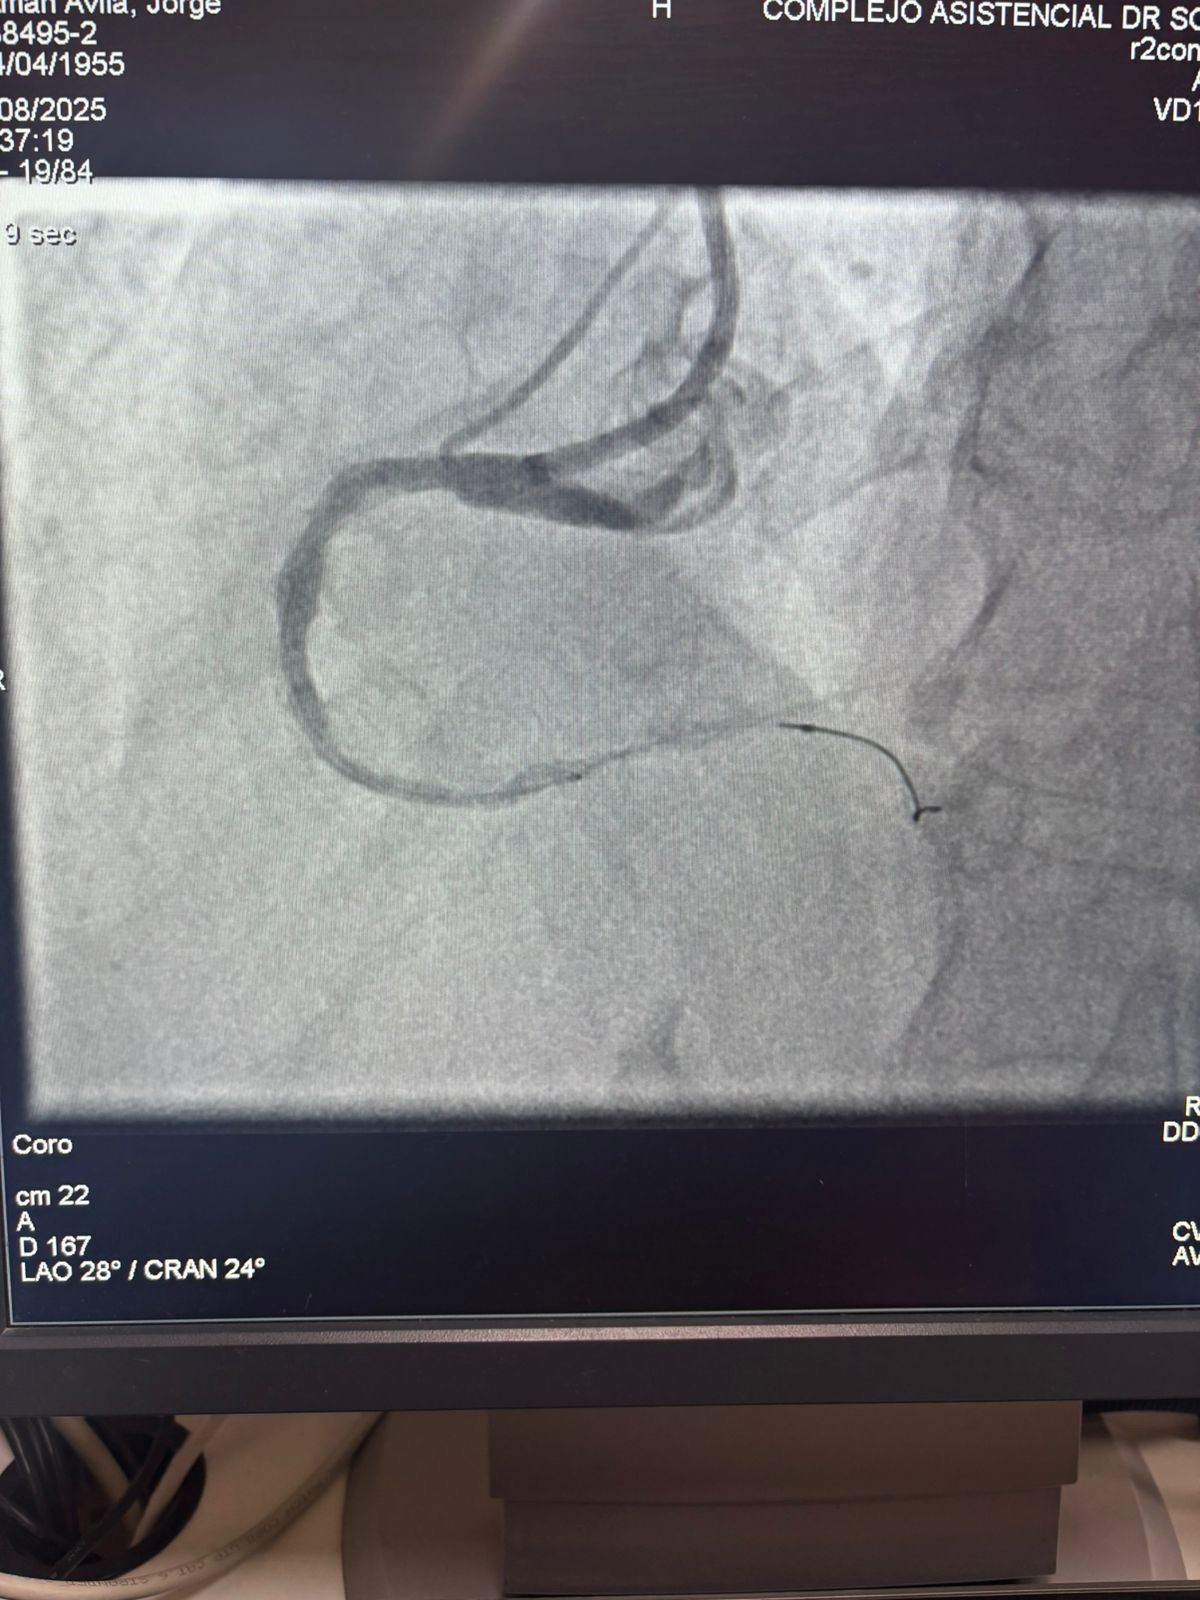

LEPU

チリのソテロデルリオ病院からの注目すべき事例を共有できることを誇りに思います。マルティンバルデベニート博士は、ベススクラック冠状動脈IVLバルーン希釈カテーテルシステムを使用して、右冠状動脈の重度の石灰化病変 (最初の曲線) の治療に成功しました。

この手順は、石灰化領域に効果的にひびが入り、血管の流れが回復し、優れた結果を達成しました。 これは、複雑な冠状動脈石灰化のための高度なソリューションへのグローバルアクセスを拡大する上でのもう1つのマイルストーンを示しています。

処置前画像と処置後の血管造影画像の比較は、当社のIVL技術の重大な臨床的影響を明確に示しています。